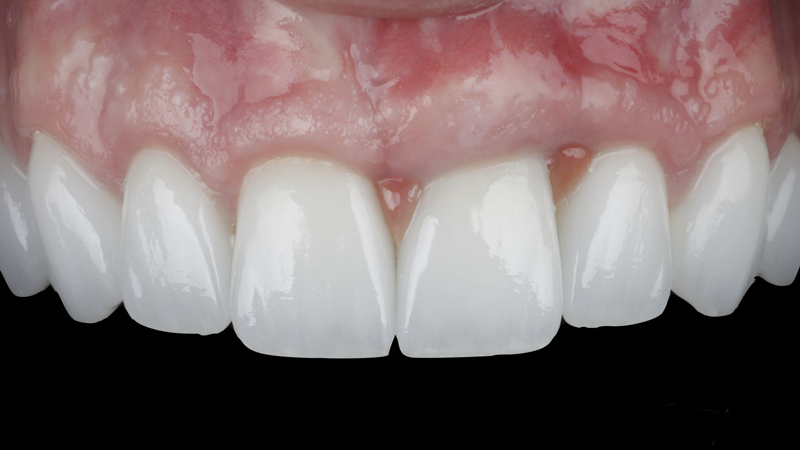

(21.) Eight-month postoperative frontal and occlusal views of the final restorations demonstrating continued stability of the gingival margin and volume.

Figure 21

(22.) Eight-month postoperative frontal and occlusal views of the final restorations demonstrating continued stability of the gingival margin and volume.

Figure 22

A patient presented for the restoration of an implant that had been placed at the site of tooth No. 9, which exhibited a residual soft-tissue deficiency and an undulating facial soft-tissue morphology (Figure 11). The objective of the treatment was to change the appearance and thickness of the facial soft tissue prior to crown placement to optimize the esthetics and prevent future soft-tissue dehiscence. After flap reflection (Figure 12), a graft was acquired from the patient's tuberosity to augment the supracrestal soft tissue (Figure 13). A volume-stable collagen matrix was then placed to further increase the thickness of the soft tissue adjacent to the implant body (Figure 14), and the flap was sutured closed (Figure 15). Following a 3-month healing period, a positive change in the soft tissue's morphology was apparent; however, its volume remained deficient when compared with that of tooth No. 8 (Figure 16). When the screw-retained crown was delivered, a second graft was acquired from the tuberosity and placed to further increase the volume of the supracrestal soft tissue (Figure 17 and Figure 18). A postoperative healing period of 4 months resulted in an ideal position of the margin of tooth No. 9 with regard to its contralateral counterpart as well as more natural looking soft-tissue morphology and excellent supracrestal soft-tissue thickness (Figure 19 and Figure 20). Eight months postoperatively, the position of the gingival margin and the thickness of the soft tissue had been maintained (Figure 21 and Figure 22).